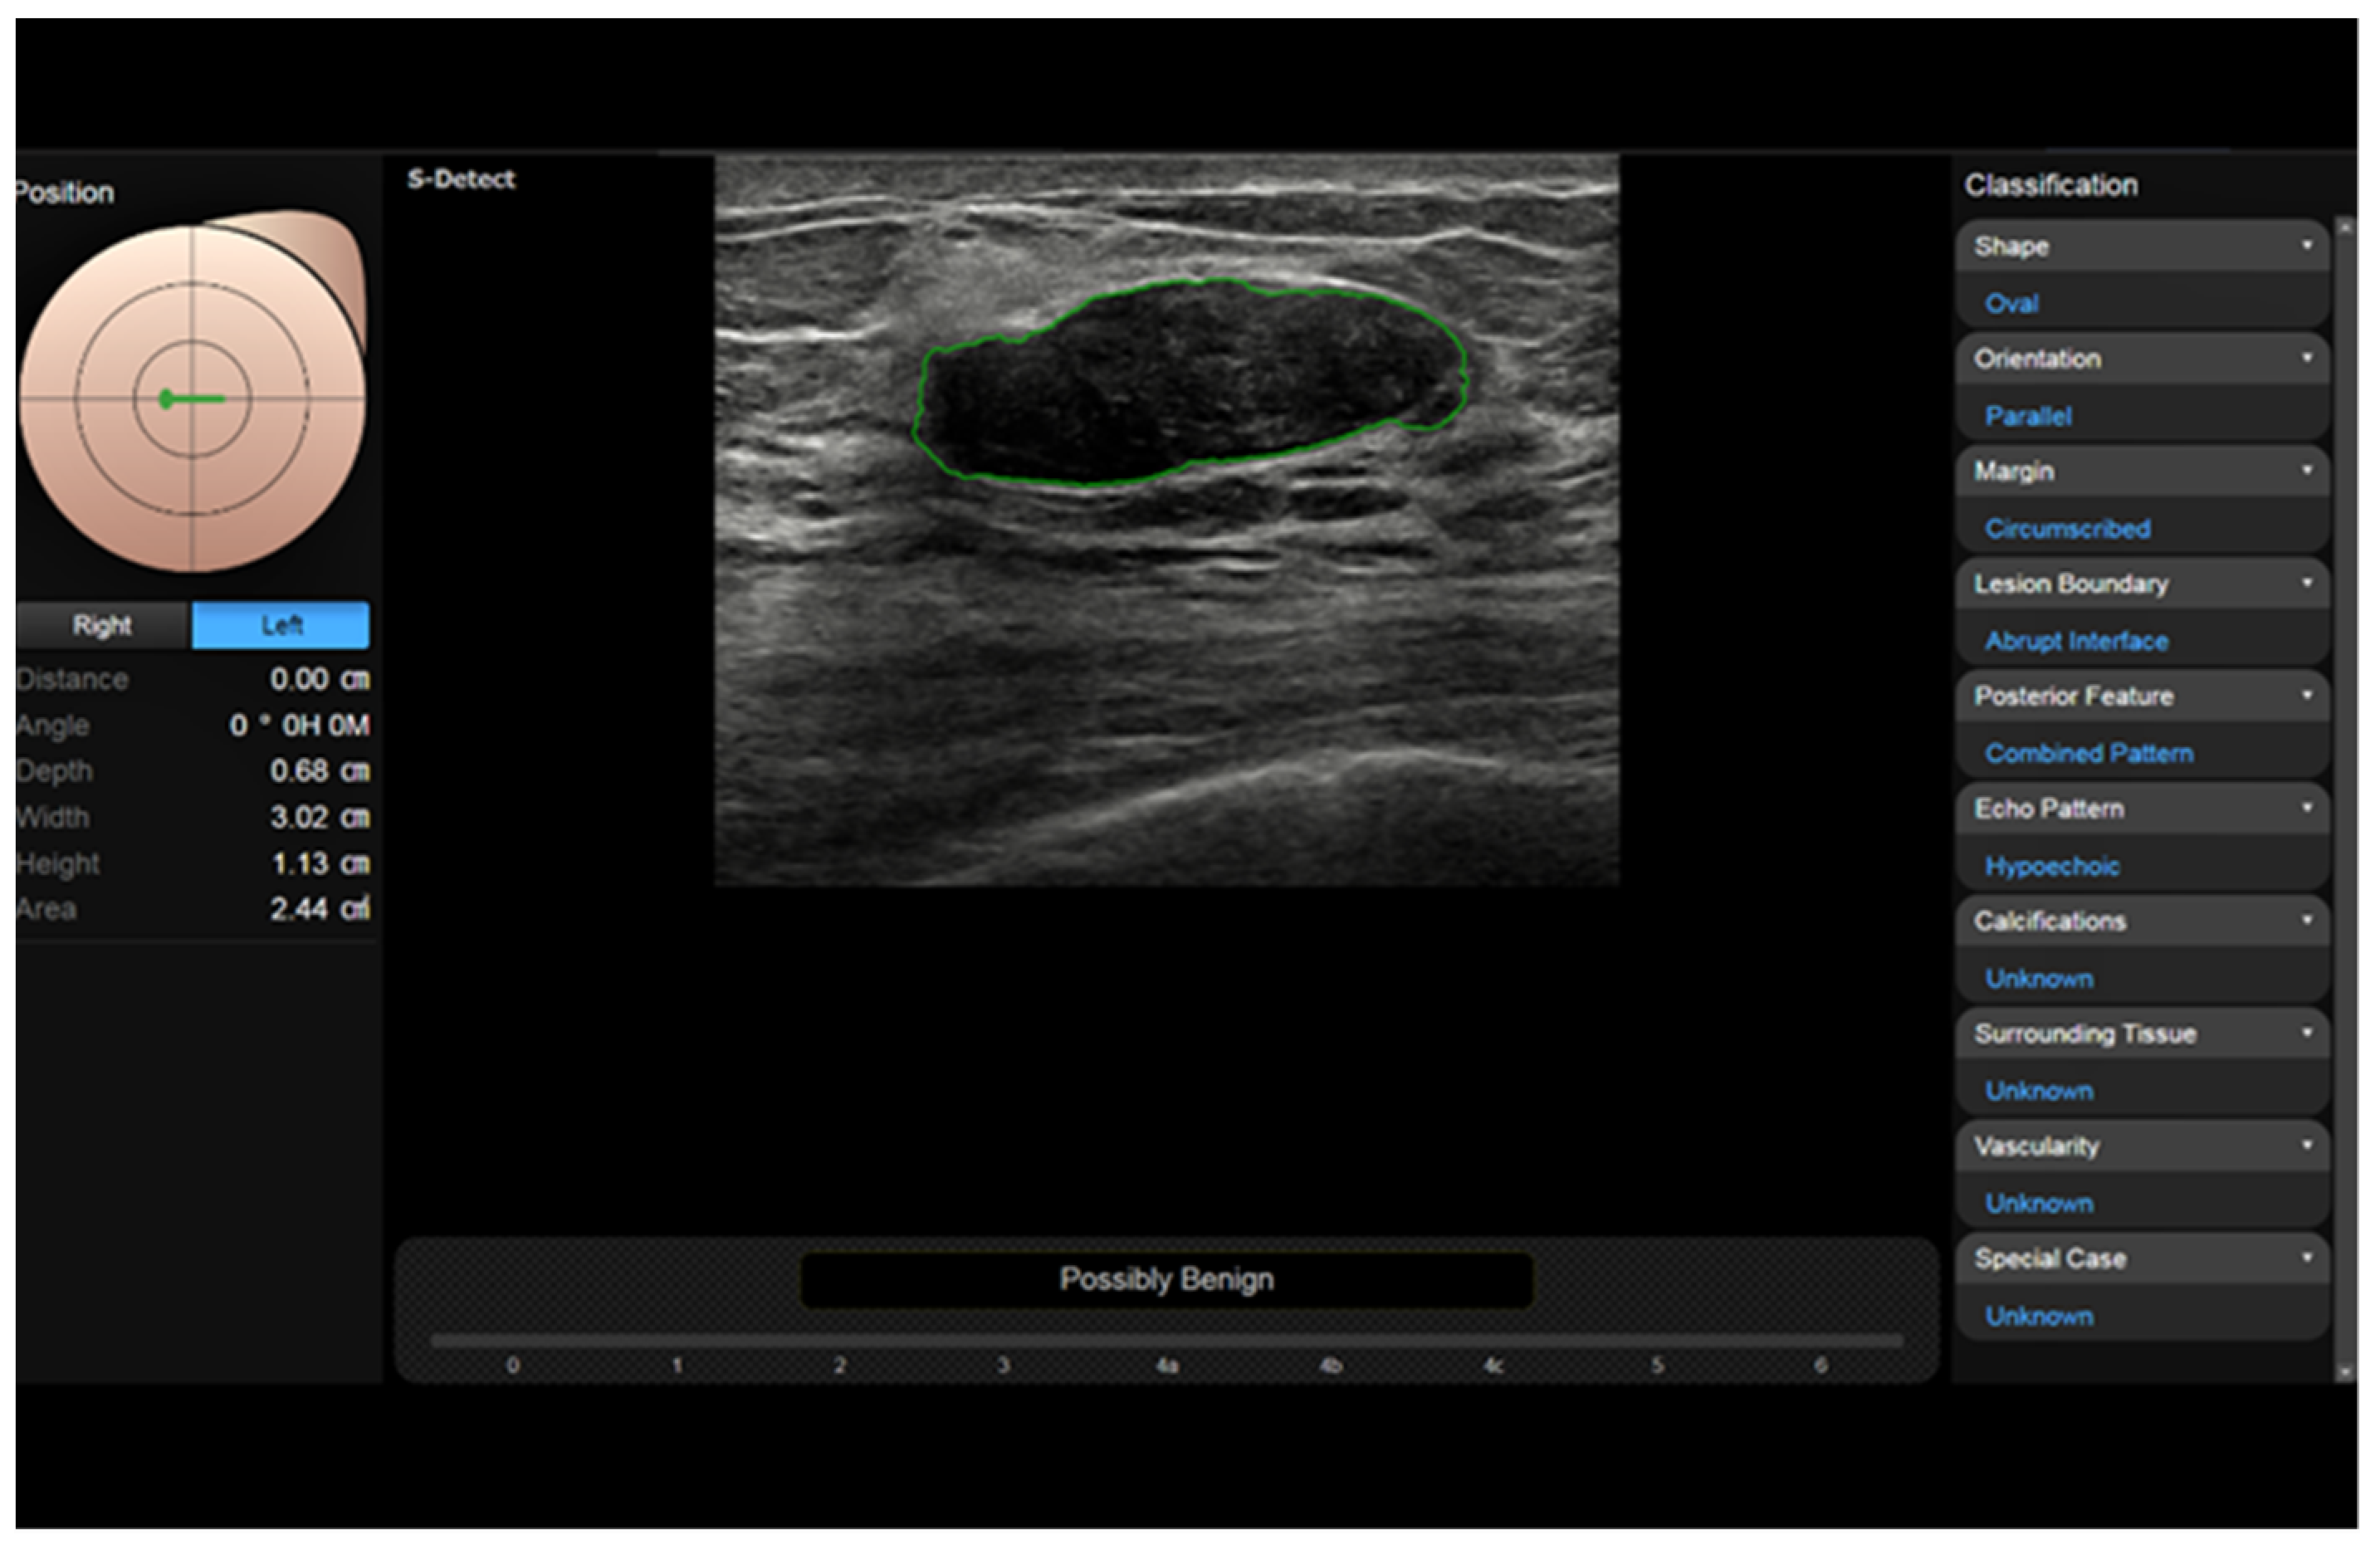

CAD systems can be offline, located in a personal computer, or inserted directly on the scanner. An example of the latter is represented by S-DetectTM, a semi-automatic tool from Samsung (Busan, Republic of Korea) [97,98,99,100]. The operator manually places a marker inside a lesion, and then, the software traces the border (adjustable) and analyzes and classifies the lesion according to the US descriptors from the BI-RADS (Figure 7).

In a study on the differential diagnosis of breast lesions, the sensitivity of five operators of different experience levels was >90% and specificity was 50–75%, while S-Detect had 90% sensitivity and 71% specificity [101]. Advanced systems are fully automatic, are based on convolutional neural networks, and have a high capability of recognizing the images.

Figure 7. S-Detect automatic measurement and categorization of a breast nodule (fibroadenoma) using BI-RADS descriptors.